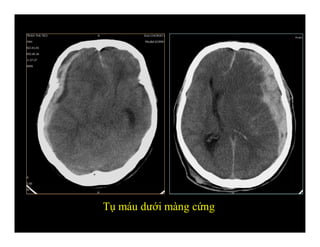

TỤ MÁU DƯỚI MÀNG CỨNG

(Subdural hematoma)

Tụ máu dưới màng cứng mãn

Phân biệt tụ máu ngoài màng cứng và dưới màng cứng